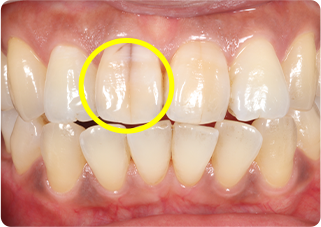

セラミッククラウン症例②

術前

仮歯

術後

| 主訴 | 前歯を綺麗にしたい、隙間が気になる |

|---|---|

| 治療期間/回数 | 4ヵ月、6回 |

| 価格(税込) | 792,000円(税込) |

| リスク・副作用 | セラミック破損の可能性 |

| ポイント | 仮歯で歯ぐきの状態を整え、自然な色、形となるようにオーダーメイドでセラミックを盛り、クラウンを作製した。 |